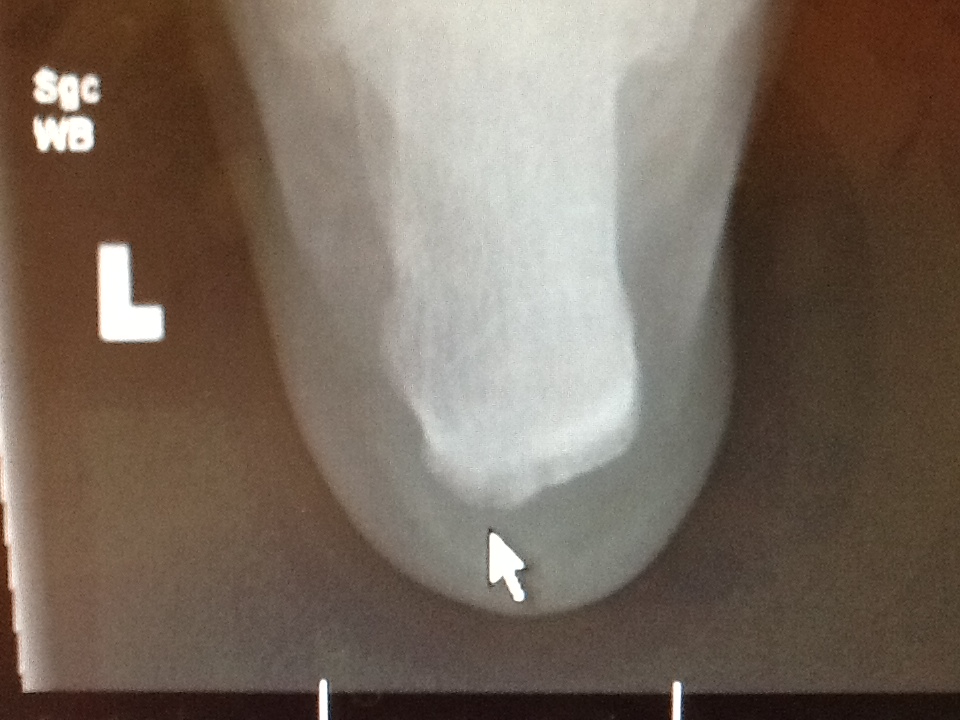

Plantar fasciitis exercises pdf spanish. A noun is a word referring to a person, animal, place, thing, feeling or idea (e.g. Instrument called a haglund’s deformity behind the heel at all. For more than ordinary heel cupping the number of forms of shock waves of low level should give you even more support. En las radiografías, se observan espolones en el talón en personas con y sin fascitis plantar.